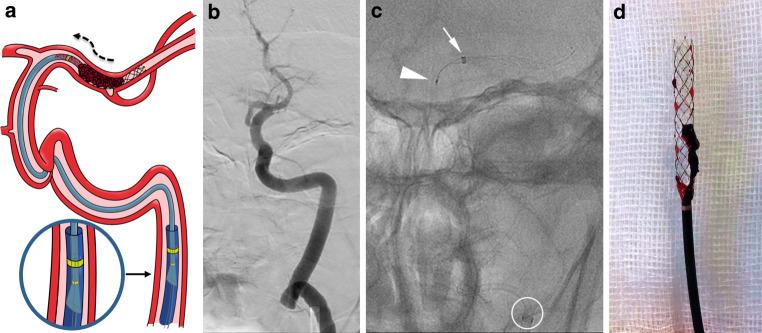

新型短鞘软抽吸导管联合支架取栓治疗脑卒中:初步临床经验。

Combined Approach to Stroke Thrombectomy Using a Novel Short Flexible Aspiration Catheter with a Stent Retriever : Preliminary Clinical Experience.

Large-bore aspiration catheters enabling greater flow rates and suction force for mechanical thrombectomy might improve outcomes in patients with stroke secondary to large-vessel occlusion. Complete or near-complete reperfusion after a single thrombectomy pass (first-pass effect) is associated with improved clinical outcomes. We assessed the efficacy and safety of novel MIVI Q™ aspiration catheters in combination with stent-retriever devices.

大口径抽吸导管能够提高机械血栓切除术的流速和抽吸力,可能改善大动脉闭塞引起的脑卒中患者的预后。单次抽吸通过(初次通过效应)实现完全或接近完全再灌注与改善临床预后相关。我们评估了新型 MIVI Q™抽吸导管联合支架取栓装置的疗效和安全性。